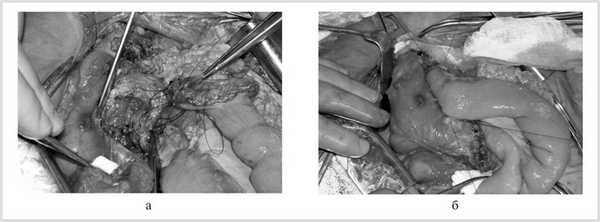

Больному выполнили вмешательство в объеме субтотальной резекции головки поджелудочной железы, используя бернский вариант операции Beger с однорядной термино-терминальной панкреатоеюностомией. Резекционный этап выполнили по известной методике, диаметр полости после резекции головки поджелудочной железы получился около 4—4,5 см. Для достижения соответствия просвета тонкой кишки диаметру полости, полученной после резекции головки поджелудочной железы, произвели продольное рассечение незаглушенного орального конца петли тонкой кишки по противобрыжеечному краю на протяжении 2,5—3 см. Далее сформировали нижнюю губу анастомоза однорядным непрерывным швом нерассасывающейся нитью пролен 3/0 (рис. 3, а). Убедившись, что продольного рассечения незаглушенного конца тонкой кишки достаточно для совмещения ее просвета с анастомозируемой полостью резецированной головки поджелудочной железы, начали формирование верхней губы анастомоза. Верхнюю губу термино-терминальной панкреатоеюностомы выполнили с помощью второй непрерывной нерассасывающейся нити пролен 3/0 также однорядным швом. При формировании анастомоза захватывали серозный, мышечный и подслизистый слои стенки тонкой кишки. В результате для создания анастомоза были использованы всего две нити. Далее находящиеся рядом концы противоположных нитей были связаны между собой без дополнительной перитонизации (см. рис. 3, б). Длительность операции 2 ч 40 мин. Кровопотеря 200 мл. Операция закончена установкой двух контрольных полихлорвиниловых трубок, которые были удалены на 2-е и 3-и сутки. На 16-й день после операции больной выписан. Рана зажила первичным натяжением.

Рис. 3. Интраоперационные фотографии. а — формирование нижней губы панкреатоеюноанастомоза; б — сформированный панкреатоеюноанастомоз.